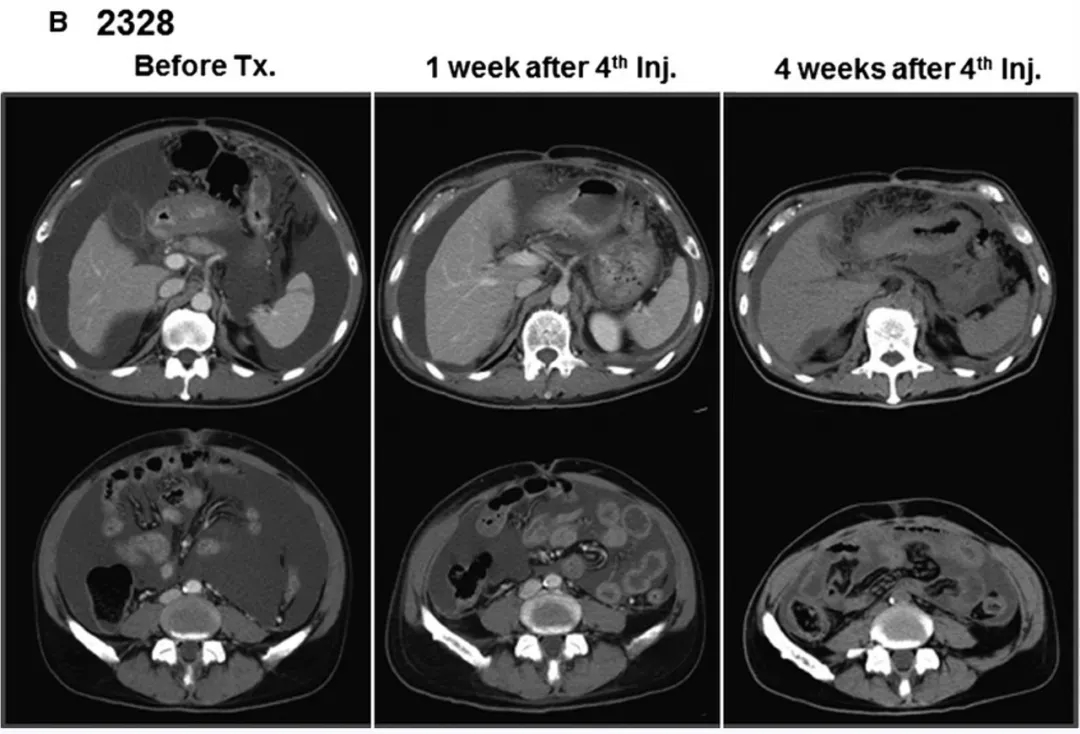

结果显示:2例可评估疗效的患者均获显著应答,临床症状大幅缓解:患者2328治疗后CT提示腹水大幅减少、近乎完全消失(详见下图B),因疗效突出追加两轮输注;患者2325的血性腹水转为清亮(详见下图C),CT同样显示腹水明显减少。

▲图源“WILEY Online Library”,版权归原作者所有,如无意中侵犯了知识产权,请联系我们删除